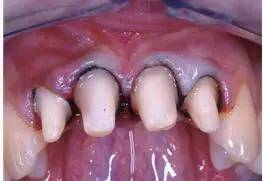

圖4 用排齦線排齦后局部粘膜發(fā)白、肩臺(tái)清晰